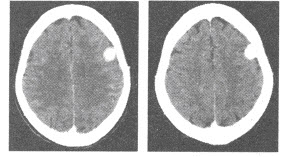

37、单项选择题 有关脏器组织增强形式与机理,错误的论述是()

A.对比剂进入血管和细胞外腔隙是组织增强的原因